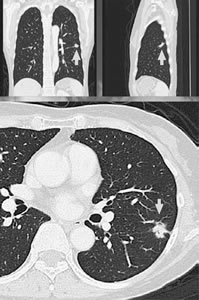

肺がんCTの断面図![]() |

矢印の先ががん

私たちは画像診断をフィルムではなくモニターを見ておこなっています。従来の横断面だけでなく、正面と側面からの縦断面も撮影し(写真)、読み落としを減らす方法をとっています。コンピューター支援診断装置の併用も検討中です。